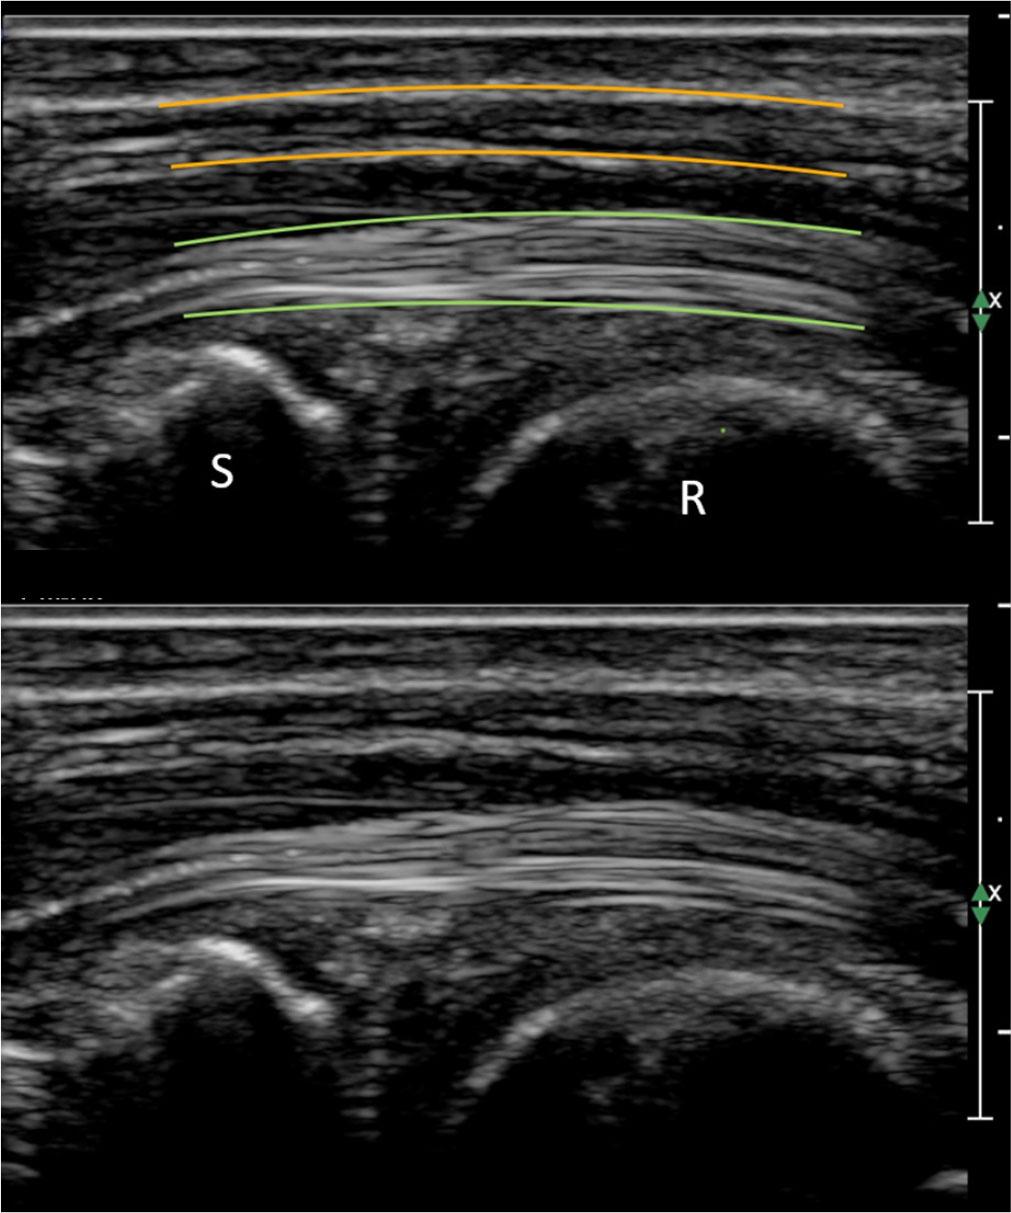

Nerves should first be traced in the short axis, with any abnormality subsequently assessed in the long axis, where their normal appearance includes parallel tubular fascicles separated by thin bright lines (Fig. 2).

Longitudinal image of the median nerve (yellow) and the underlying flexor tendon (green) within the carpal tunnel. The distal radius (R) and scaphoid (S) can be seen at inlet. Note the tubular appearance of the nerve, contrasting with the linear fascicular appearance of the underlying tendon